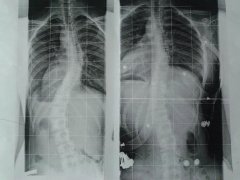

Gestern hatten wir den spannenden Kontrollröntgen Termin bei Rahmouni. Meine Tochter und ich waren von 6 Uhr früh bis Mitternacht unterwegs. Doch als ich das RB sah fiel mir ein Stein vom Herzen. Endlich mal eine gute Korrektur. Findet ihr nicht auch? Rahmouni hat sie sehr gelobt wegen der guten Tragezeiten (15 bis 18 Stunden) Leider hab ich noch keine Gradangaben, bekomm ich hoffentlich morgen von Dr. Hoffmann.

- b94b991c.s.jpg (9.24 KiB) 19242 mal betrachtet

Hmmmm wenn rechts das neue ist , steht sie aber gut aus dem Lot.......

Ach sorry, links ist das Röntgen vor 6 Wochen ohne Korsett und rechts das aktuelle mit Korsett. Jetzt muss ich mich noch um 1,5 cm Schuherhöhung kümmern. Wir wohl schwierig werden da Schuhe für eine 14jährige zu finden!!

Die Korrektur ist super, schön sichtbar.